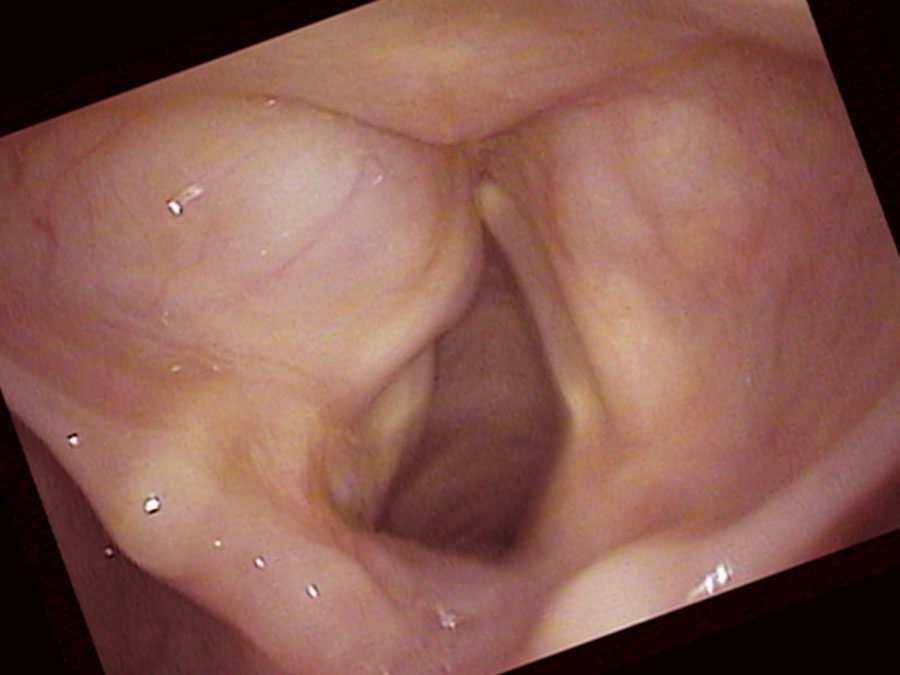

Indeed, I find one of these possible explanations when I look with the endoscope: her left vocal cord is not moving well. It is not opening and closing very much during breathing nor during voicing. However, it does sit near the midline. Sorting out her case requires thinking about a few complexities. She can almost close the right vocal cord against the left, so she has already compensated quite a bit for the paralysis.

I ultimately numb her vocal cords so that I can place my endoscope underneath the smooth, round, swollen left false vocal cord. The left false vocal cord is dilated and obscures the left true vocal cord. There is a fluid-filled cyst enlarging the left false vocal cord. The left vocal cord is also not moving and in the view during inspiration, the left vocal cord remains positioned near the midline. Even on a close-up view it is difficult to see the left true vocal cord. I actually have to lift the swollen false vocal cord up with the endoscope to see the true vocal cord.

The saccule is a gland located on the bottom of the false vocal cord at the front of the larynx. Usually the saccule cannot be seen from above. However, occasionally this gland may plug and fluid accumulates inside it. The saccule swells with its own fluid creating a saccular cyst. Now we must consider that we have a complex problem: a left vocal cord that is not completely paralyzed — it moves some. So there is synkinesis of the left vocal cord. The right vocal cord closure has compensated to the point that she can bring the two vocal cords together. Consequently, even though the left cord’s neurologic injury is visually obvious, since the right vocal cord closes against the left during sound production, they are not causing air leak (husky hoarseness). Since the left cord has reinnervated, it also has the same bulk as the right vocal cord and so it is not causing diplophonia (rough hoarseness).